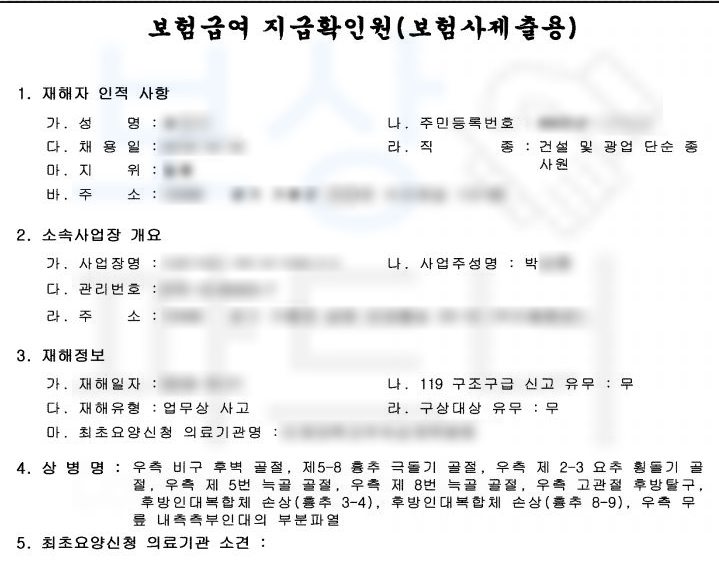

그럼 실제로 보상 파트너가 처리한 추락 사고로 고관절 후방 탈구 및 비구 후벽 골절 진단받은 강@@님의 보상 사례 소개해드리겠습니다. 보상 파트너로 연락 주신 강@@님은 주택 리모델링 현장에서 용접 작업을 하시던 중 용접 부분이 이탈하면서 2M 아래로 추락하는 사고를 당하셨습니다.

이 사고로 인해 재해자는

골반부의 고관절 후방 탈구 및

비구 후벽 골절 진단을 받으셨고 응급실에서 도수 정복 후 비구의 골절이 심한 상황이었기에 금속판 내 고정술을 시행하셨습니다.

전치 12주 진단받아 병원에 입원하며 요양을 하셔야 했죠. 산재 보험 처리와 개인적으로 가입해두신 보험에서도 추가 보상받을 수 있습니다. 보상 파트너가 말씀드리는 보상은 장해 보상만을 가리킵니다!

회사의 협조로 무사히 산재처리를 진행하셨던 강@@님은 치료 이후에도 여전히 고관절의 움직임에 불편을 호소하셨습니다.

통증과 운동 제한이 남게 된 거죠. 산재 장해보상은 평가되어야 할 장해부위가 누락 없이 검토되는 것이 중요하며 장해 진단을 하는 전문의가 장해 판정 기준을 올바로 알고 객관적이고 공정한 측정이 중요합니다.

보상 파트너는 재해자의 신체에 잔존한 고관절의 운동 장해에 대해 올바르게 장해 평가가 될 수 있도록 산재 종결 시점 병원에 함께 내원하여 도와드렸고 보상 파트너와 함께 장해 평가를 진행하신 결과

다리의 1개 관절의 단순 기능장해 **제12급 제10호 **인정받을 수 있었습니다.

산재 장해급여 33,726,000원이죠. 의뢰인은 손해보험사에 일반상해 후유 장해 항목으로 1억 원 가입되어 있으셨습니다. 보상 파트너는 피보험자의 보험 증권을 받아 가입시기 및 약관을 분석하였고 개인보험 역시도